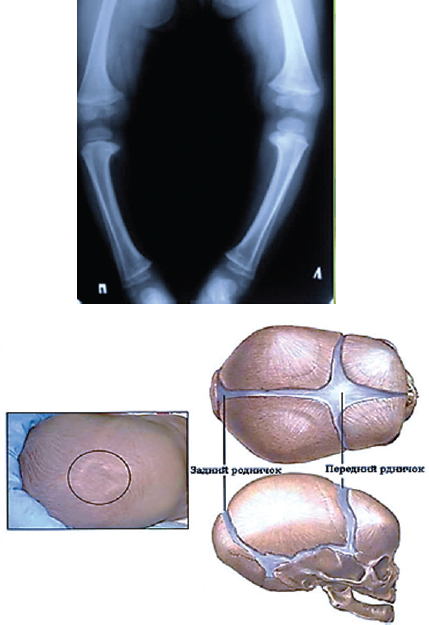

Ранний рахит характеризуется преимущественным поражением интенсивно растущих отделов скелета. Так, в костях черепа возникают размягчения и остеофиты, в результате чего голова ребёнка приобретает форму четырёхугольной башни. Появляются рахитические чётки и браслетки на ребрах. В трубчатых костях происходит рассасывание костных пластинок, корковый слой срединной части (диафизов) костей истончается, в результате чего они легко искривляются (рис. 14).

Рис. 14. Деформация частей скелета и задержка закрытия большого родничка при рахите / Fig. 14. Deformation of parts of the skeleton and delayed closure of the large fontanel in rickets

Поздний рахит. Основные изменения костей возникают внутри кости. Кости нижних конечностей и таза деформируются, грудина приобретает форму грудного киля птиц – возникает «петушиная грудь».

Проявления. Различают: ранний рахит – у детей от 3 мес до 1 года; поздний рахит – у детей от 3 до 6 лет; рахит взрослых или остеомаляцию. Для рахита характерна триада изменений: 1) нарушения в зоне роста кости (то есть нарушение превращения хряща в кость) и избыточное образование хряща в этой зоне; 2) чрезмерное накопление костной ткани со стороны хряща и надкостницы; 3) нарушение процесса обызвествления в растущих костях, остеопороз и остеомаляция в связи с уменьшением в костной ткани солей фосфора и кальция.